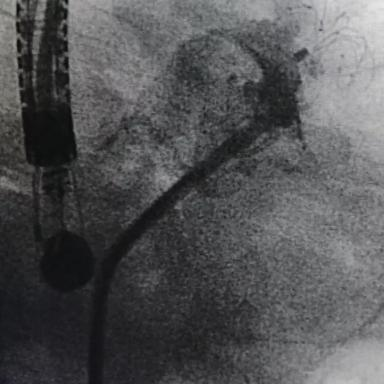

2021年9月12日中午13时许,左心耳封堵术正式开始。首先唐琪老师在TEE下,排除了心房室结构及左心耳内血栓存在的风险,同时在多角度下对左心耳封堵器的锚定区和开口区进行了测量。随后在李耀东教授及王继伟副院长的带领下行房间隔穿刺,房穿后鞘管轴向极佳,即刻对左心耳进行了造影,结果显示左心耳形态呈鸡翅菜花型,测量后锚定区24mm,封堵区32mm,综合评估后选用LAmbre™ 2834封堵器进行封堵。DSA和TEE下显示无残余分流,牵拉稳定,完美封堵,整个手术用时仅40余分钟。